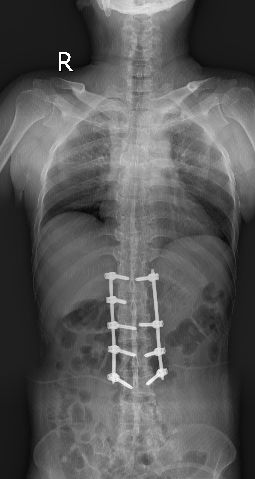

深圳市中医院骨三科的何升华主任经过仔细的检查、看片以后得出诊断结论:病人为强直性脊柱炎合并L1、L2椎体爆裂骨折。

全脊柱正侧位显示骶髂关节间隙消失

脊柱竹节样融合改变

经过骨科的术前讨论,征求了家人的同意,何升华主任制定了经皮椎弓根螺钉内固定联合过伸体位下弹性按压手法复位的中西医结合的微创治疗方案。

术中何升华主任采用经皮微创方法植入椎弓根螺钉

2月28日顺利实施手术,术中将传统的中医正骨手法与现代化的经皮椎弓根螺钉植入技术相结合,经腰背部脊柱两侧各打4个小洞便顺利完成世界级的高难度手术。

术后复查见腰1、腰2椎体高度恢复,螺钉位置满意